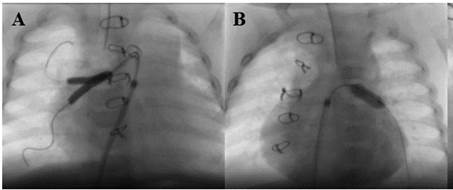

electrocardiogram (Figure 2) showed sinus tachycardia and the chest X-ray

showed cardiomegaly and overt signs of bilateral flow redistribution. During

Fig.

2. A. Electrocardiogram on admission showing sinus

tachycardia. B. Electrocardiogram at discharge showing sinus rhythm, normal

heart rate with increased voltages in general and a more marked difference in

right precordial leads.

origin to continue with the rehabilitation in the general ward, with an ECG

evidencing increased voltages (Figure 2) and a TTE showing completely normalized

biventricular function.